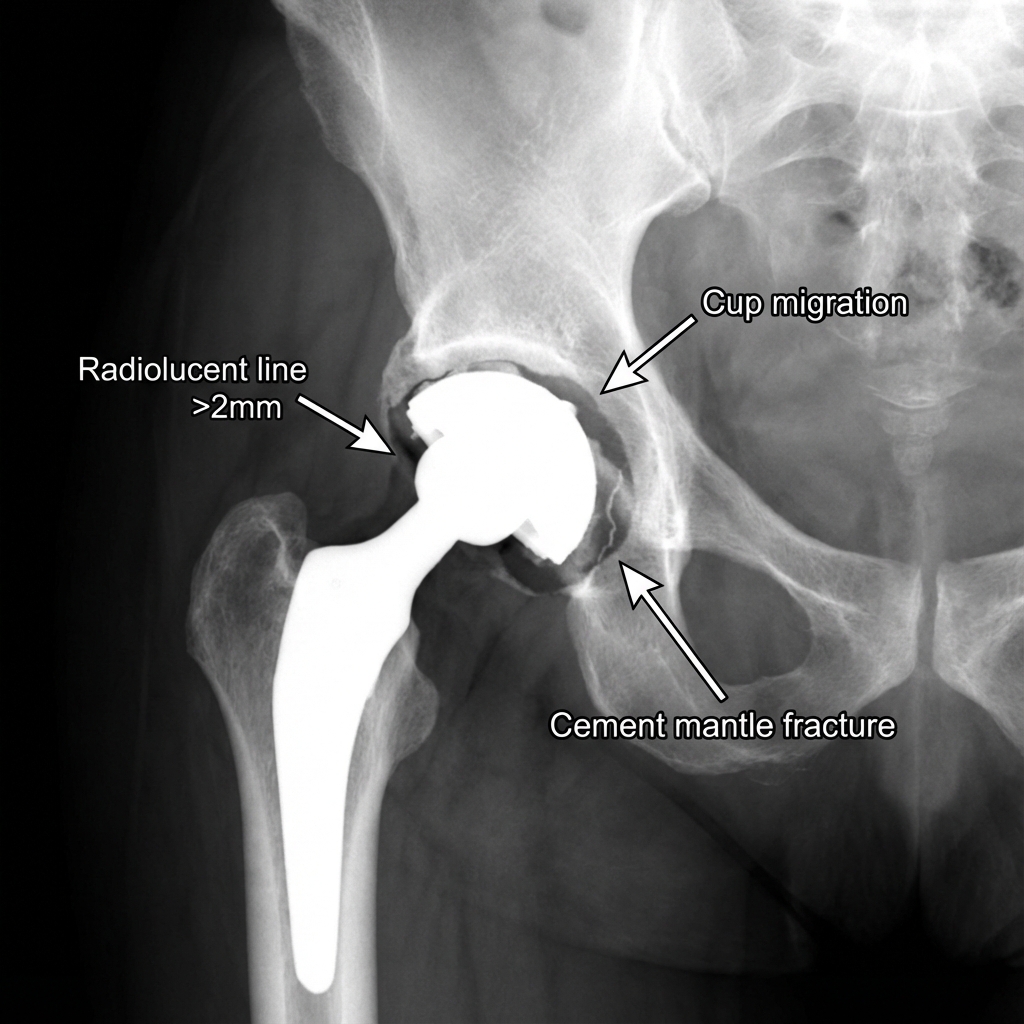

AP pelvis radiograph showing left cemented THA with progressive radiolucent line >2mm around acetabular component, cup migration, and cement mantle fracture. Femoral component appears well-fixed.